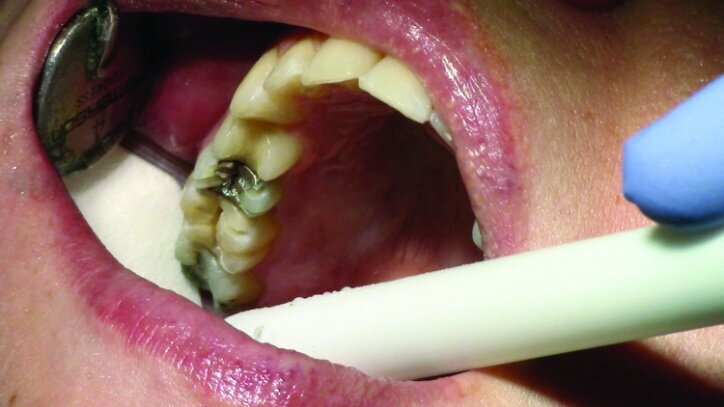

The remainder of the existing composite resin in #3 and the amalgam in #4 were removed. The occlusal surfaces of the preparations were blended into the interproximal areas using a KS2 bur to create smooth preparations (Figs. 10–15c). There was no retention or resistance form prepared to retain the restorations.

Tissue management was obtained with ViscoStat Clear, gingival haemostatic gel, 25 percent (m/m) aluminum chloride (Figs. 16 & 17). Gingival retraction was obtained using a two-cord system. First, a #00 size cord from Ultradent was placed on the mesial and distal of both preparations (Figs. 18 & 19).